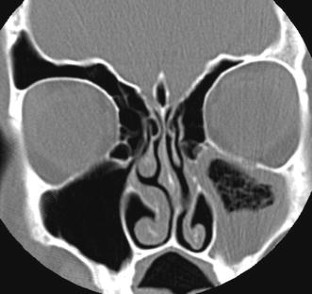

Fig. 2